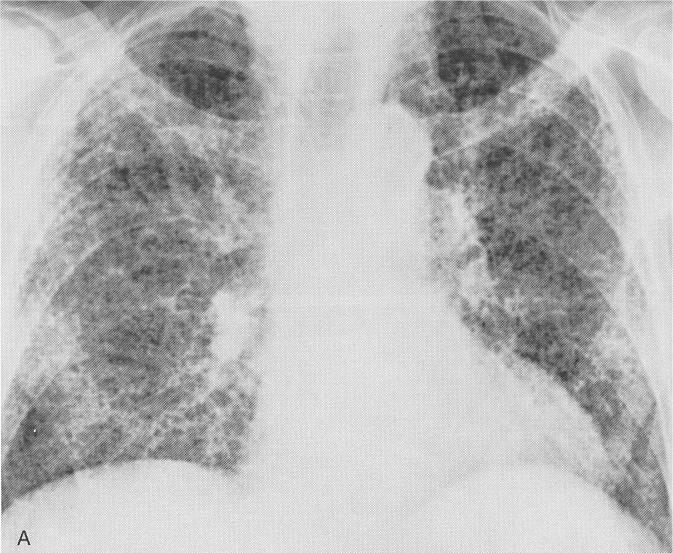

La fibrosis pulmonar es el daño que resulta al cicatrizar el pulmón después de una inflamación, usualmente no causada por una infección. Se caracteriza por una cicatrización progresiva (fibrosis) que hace que el pulmón pierda flexibilidad, y se deteriore su funcionamiento a lo largo del tiempo. Es típico que la radiografía de tórax revele la presencia de opacidades reticulares difusas en las zonas inferiores y periféricas del pulmón. Suele afectar en mayor medida a personas que tienen entre 50 y 70 años. También se conoce como enfermedad pulmonar intersticial. La fibrosis pulmonar es una enfermedad que se produce cuando el tejido pulmonar se daña y se producen cicatrices. Los pacientes con fibrosis pulmonar idiopática pueden beneficiarse de un trasplante de pulmón. La fibrosis pulmonar idiopática (fpi) es una enfermedad huérfana limitada al pulmón que causa un daño progresivo a la función pulmonar de quienes la te puede interesar: La información que ha suministrado es incorrecta. Al ocurrir esto, se dificulta la recepción de oxígeno a la sangre, por lo tanto recuperar el aliento se. Causas de la fibrosis pulmonar idiopática. La fibrosis pulmonar idiopática (fpi), la forma más común de neumonía intersticial idiopática, causa fibrosis pulmonar progresiva. En la actualidad, la fpi afecta entre 14 y 43 personas por cada 100.000, y se estima que.